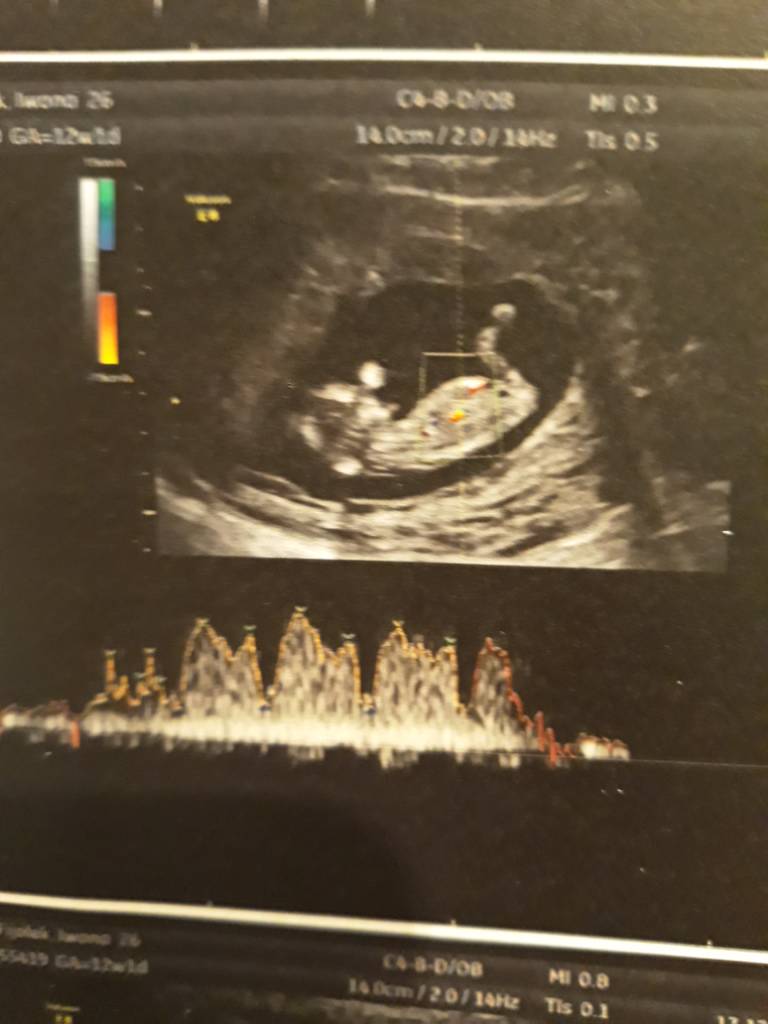

A no i dolaczam zdjecia moich Kabanoskow - jeden leniuszek ladnie pozowal a drugi wyglada jak kosmita bo sie ruszal , dzis tez do mnie machal !

A no i dolaczam zdjecia moich Kabanoskow - jeden leniuszek ladnie pozowal a drugi wyglada jak kosmita bo sie ruszal , dzis tez do mnie machal !ale z dzis zdjec nie mam bo to byl szybki.poglad ze wzgledu na upadek... aaa plecy bola ;(